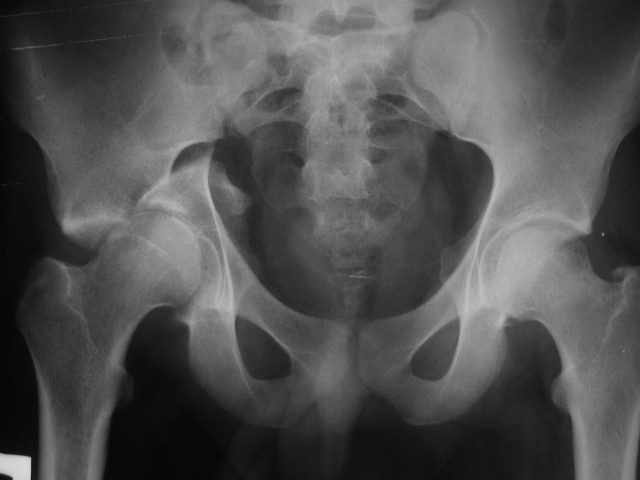

Уважаемые коллеги!Молоодой человек 20 лет,задний вывих правого бедра, поперечный перелом и перелом заднего края правой вертлужной впадины. Самое сложное то, что после травмы уже прошло 8 недель. Планируем ввыполнить остеосинтез из двух доступов (задне-боковой и подвздошно-бедренный). Если у кого есть опыт остеосинтеза впадины из двух доступов посоветуйте с какого лучше начинать в данной ситуации. Алексей.

Какой доступ вам более известен, но для совета нам надо определится с переломом, на половине обтуратор косой проекции не все элементы видны.

Есть ли другие снимки, пришлите на сайд-прямой таз, две косых: обтуратор и подвздошный Judet views, затем можно поговорить о доступе.

Все тебе два доступа сделать хочется, а зачем неясно. Снимки обрезанные, видно огромный фрагмент заднего края. Он повидимому и является ключем стабильности. Если перелом передней колонны низкий, на него можно не обращать внимание, так что возможен вариант восстановления только задней колонны из задне-бокового доступа, даже без остеотомии вертела. Особое внимание на сохранение питания отломка.

Пришли все-таки нормальные снимки, тогда может быть станет понятны твои проблемы, зачем тебе изнутри забираться, пока это очень и очень сомнительно.

Послал все снимки но видимо не все дошли. досылаю